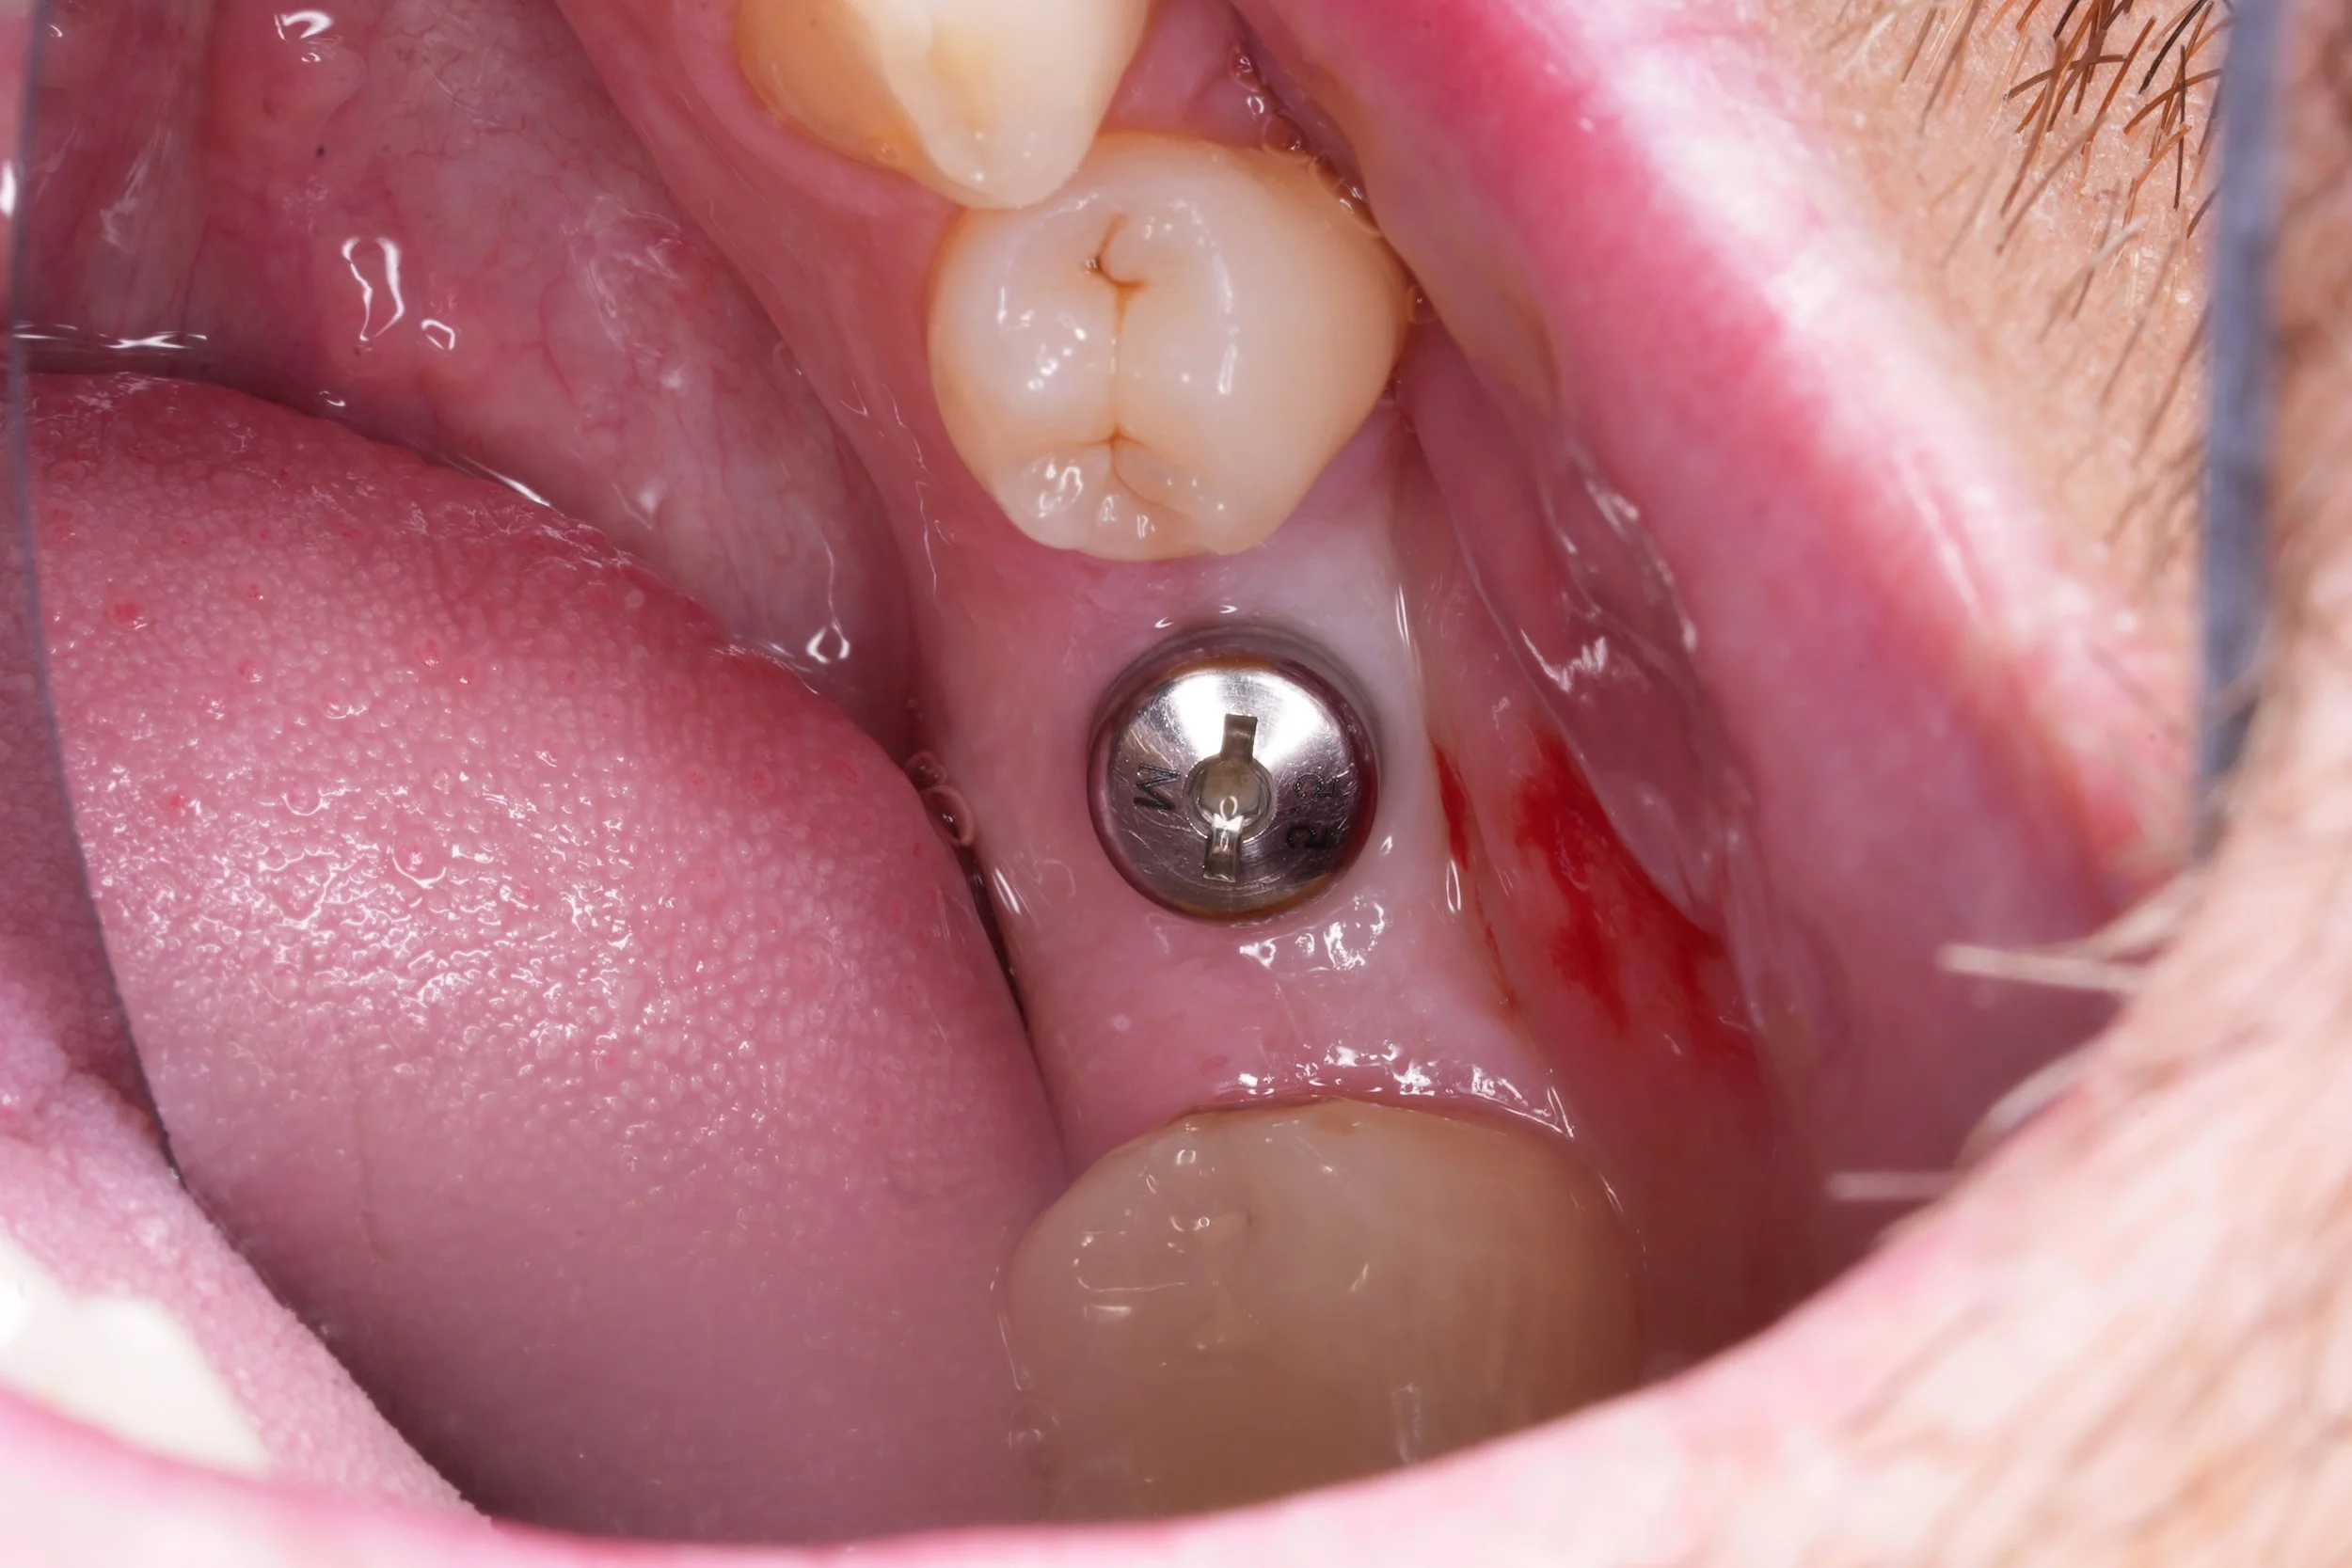

Dental Implants